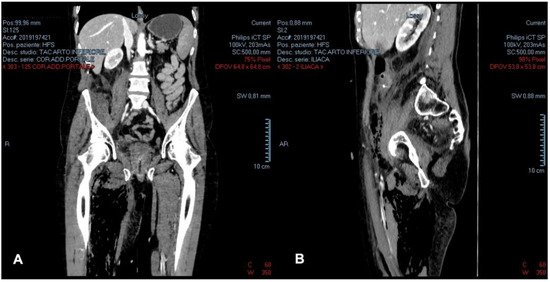

2.1. The Clinical, Surgical, and Radiological Data